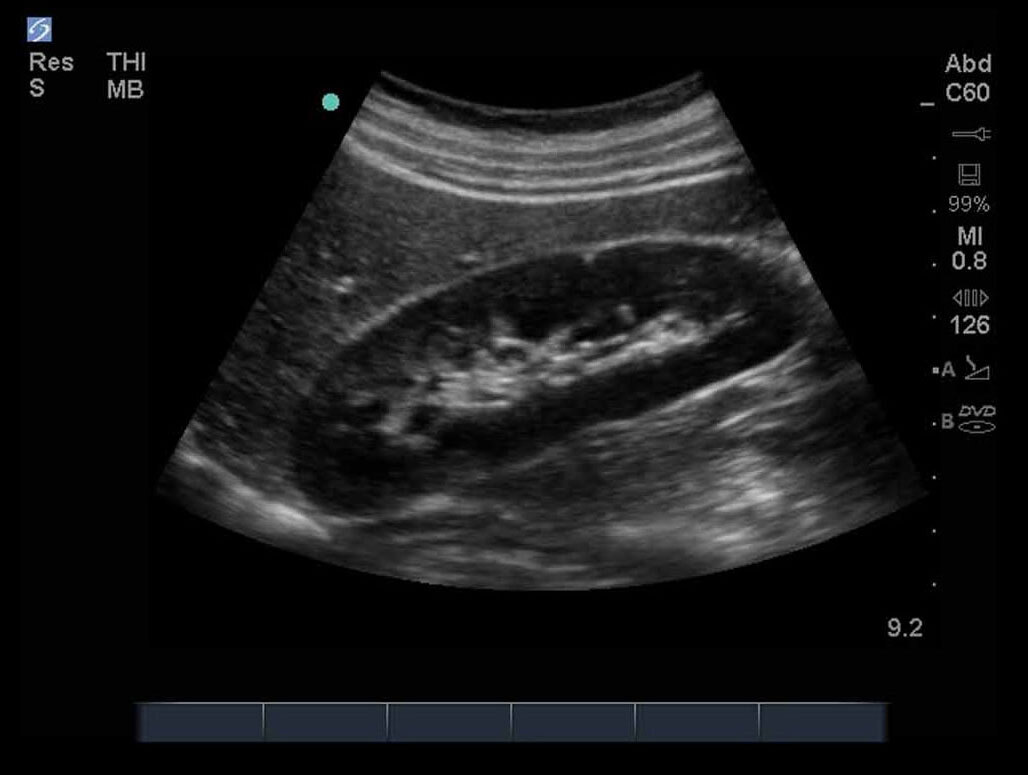

FAST Right Upper Quadrant (RUQ) 1 Image

M-Turbo: FAST Exam, Right Upper Quadrant 1.